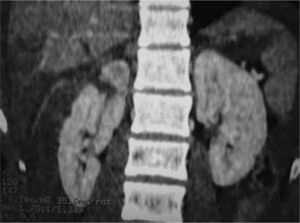

Es una herramienta importante en el manejo del trauma abdominal y abdominopélvico cerrado. Se encuentra reservada para los pacientes hemodinamicamente estables y que puedan ser trasladados al tomógrafo, y tolerar el estudio (3, 9, 10). Se debe utilizar medio de contraste oral e IV (3, 9, 10). La TAC puede determinar la presencia de lesiones en órganos sólidos, líquido intrabdominal, sangre, aire y lesiones en los órganos retroperitoneales, los cuales pueden haber sufrido con el trauma y no provocan hemoperitoneo, por lo que no son detectados con el ultrasonido (3, 10), como también mostrar la extensión de la lesión en estructuras como el bazo e hígado, así como determinar la extravasación de contraste, que implica sangrado activo (3, 9). Debido a estas características, la TC es muy útil para decidir el manejo terapéutico de la lesión (3, 8). De todas maneras el valor de la administración de contraste oral para el diagnóstico de perforación de víscera hueca es dudoso, y se encuentra asociado al riesgo de broncoaspiración, por lo que no debe realizarse de rutina (3). La TC tiene una sensibilidad de 92 a 98% y una especificidad de casi 99% en la detección de lesiones de órganos sólidos (3). No detecta lesiones de diafragma, intestino y algunas de páncreas (3, 9). Debe tomarse en cuenta la experiencia del radiólogo que interpreta el examen (8).

Figura 4 Trauma hepático. Figura 5 Trauma renal. Figura 6 Lesión del sistema colector con urinoma de la pared.